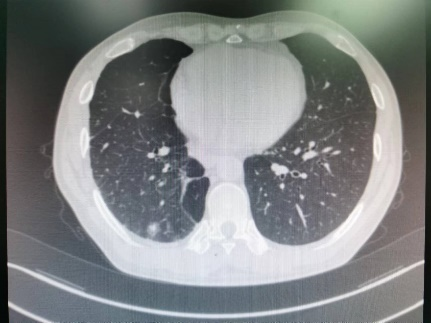

胸外科成功实施肺肿瘤“冷冻消融术”

近日,我院胸外科成功完成2例肺恶性肿瘤术后复发/转移肿瘤的冷冻消融术。两位患者均恢复良好,目前已出院。 51岁的辛先生和74岁的汪女士均为我院胸外科的肺癌术后随访6年的老患者,辛先生在上月体检时行胸部CT检查发现自己的右侧肺部竟再次长出一个直径约1....